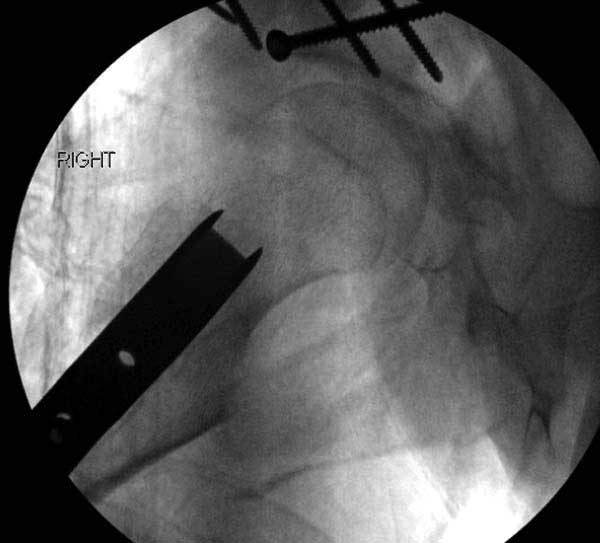

Первым этапом сделана подготовка к ротационной межвертельной остеотомии, затем капсулотомия с удалением импинджмента и периацетабулярная остеотомия с 40 градусной экстензией и операция закончена 35 градусной наружной ротацией бедра. Запланированный варус не сделан из-за относительно нормального покрытия головки.

Одним из преимуществ ПАО является сохранение задней колонны, и всю фиксацию в основном делают спереди из крыла подвздошной кости. При реконструкционных операциях по поводу дисплазии редко коррекция превышает 25 градусов, и достаточной бывает фиксация тремя шурупами вертикально сверху вниз, и один между колоннами спереди кзади. Но у нашего пациента серьезные изменения, и для достижения результата надо было около 40 градусов коррекции, из-за чего в линии остеотомии создалась ступенька. Для предупреждения скольжения дополнительно установлена buttress пластина, которая зафиксирована только в одном сегменте, а другие два шурупа удерживают ASIS. Без остеотомии Anterior Superior Iliac Spine невозможен доступ внутри таза.